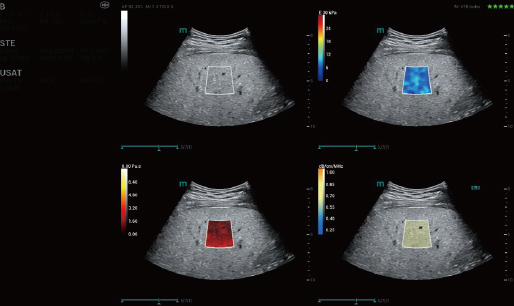

STVi enables the quantitative evaluation of tissue viscosity and

provides real-time multi-parameter imaging, offering a more

comprehensive approach to imaging diagnosis and quantitative

analysis of chronic liver diseases, breast lesions, and other

conditions.

Dual quantitative coefficients

Chronic liver disease assessment

Multiple quantification tools

Breast tumor assessment